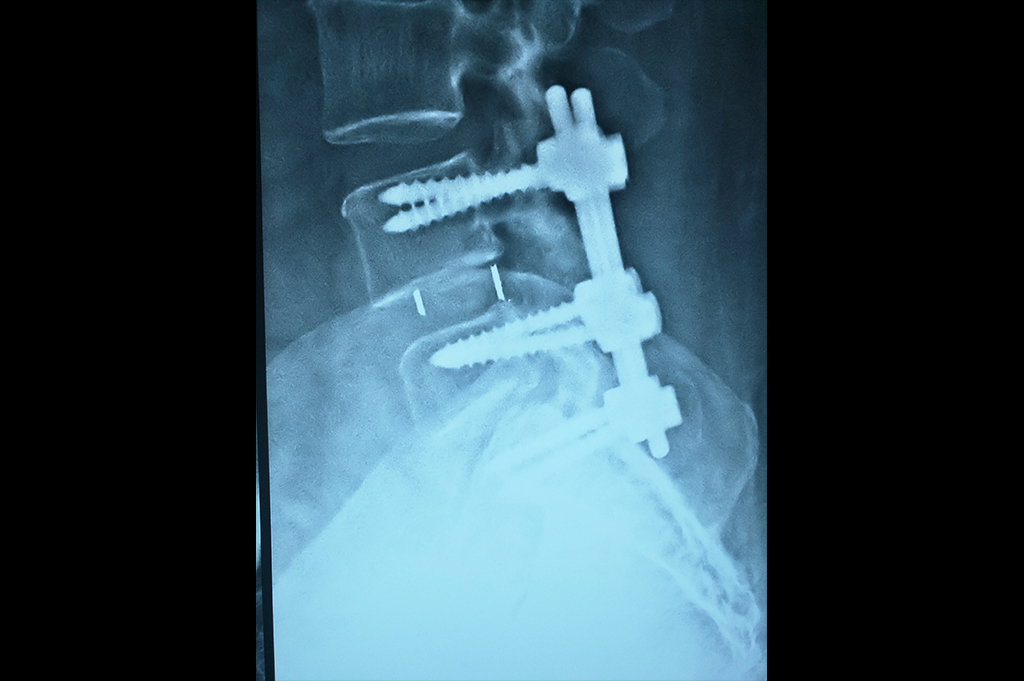

Spine